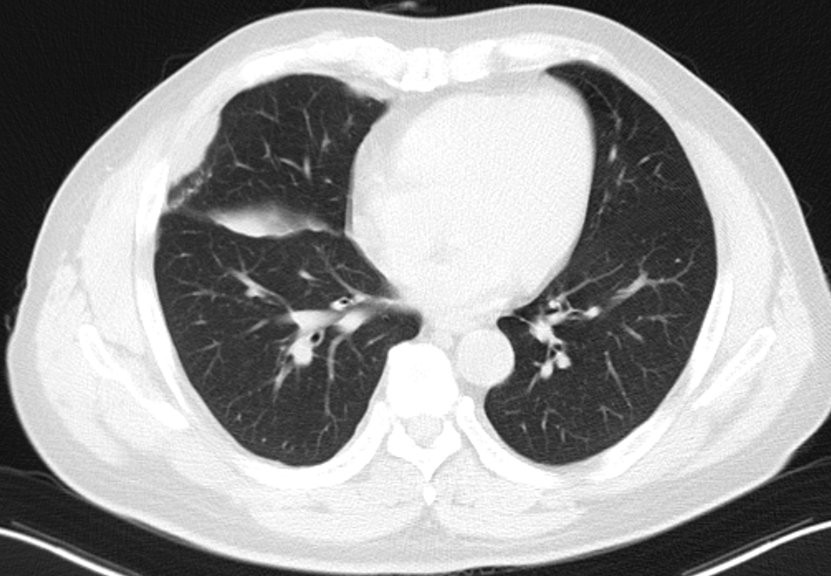

患者男性,56岁,因反复咳嗽入院 2016.12.22行胸部CT检查提示:右侧胸膜为广泛增厚呈不规则状、结节样的增厚,右侧胸腔可见有大量的胸腔积液。纵隔、肺门淋巴结不大,考虑胸膜间皮瘤可能。于2017-1-10行VATS右胸膜活检术,术后病理提示(右胸膜)恶性肿瘤,结合酶标结果考虑恶性间皮瘤。免疫组化结果:TTF-1(-),NapsinA(-),CK7(+),WT-1(+),CK5/6(+),CAL(+),MC(+),D2-40(+)。术后恢复良好,术后予抗炎、补液等对症治疗,诊断为:右侧胸膜间皮瘤cT4N1M0-IIIB期。患者于2017-2至2017-5行AP(培美曲赛联合顺铂)方案化疗共4周期。2017-6-27胸部CT检查提示疗效部分缩小(PR)。